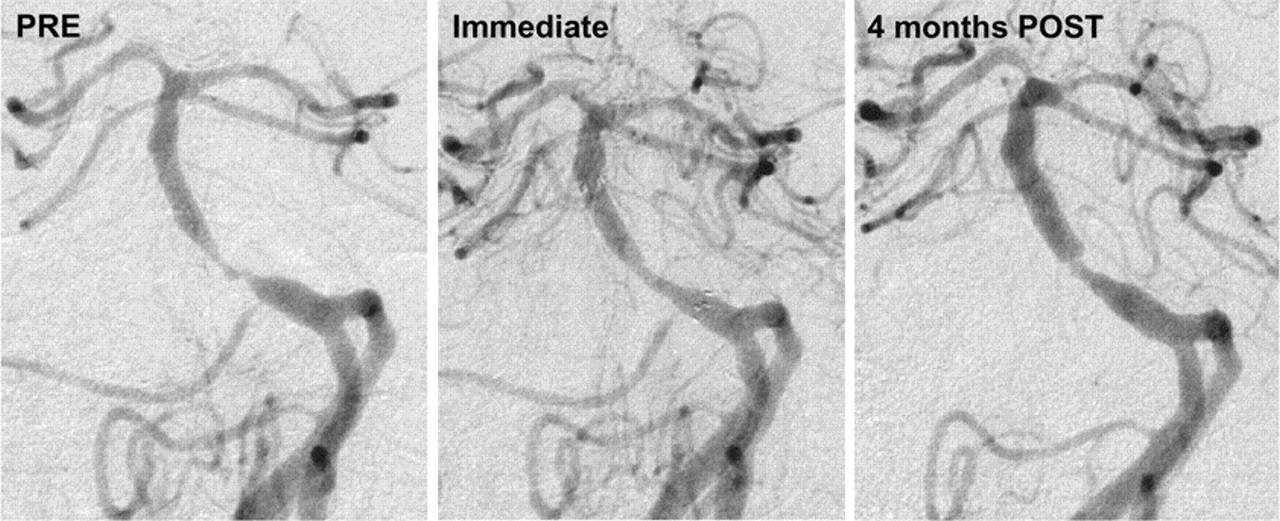

支架后的颅内动脉的MCA 33%,颈动脉26%,椎动脉24%,底动脉17%。技术成功率为96.7% (95% CI = 91.8%到99.1%)。意思是pre-stenting直径狭窄82%±9%(值80%,质量75%和90%)和直接的意思是支架植入后残余狭窄20%±16%(值20%,质量10%和30%)。共有52名患者(40%)在平均随访脑血管造影术4.8±2.1个月后支架(四分位数3.4和6.3个月)。平均残余狭窄血管造影术率为29%±28%(值20%,质量10%和48%)。再狭窄(≥50%)被发现在13/52(25%)的患者(6 50 - 69%和7 100%到70)。再狭窄患者的13个,2/13中风(都归因于支架阻塞):一个病人,中风在2个月,已经起飞阿司匹林和氯吡格雷5周后支架植入手术,只有阿司匹林是重启;阿司匹林和氯吡格雷的其他患者支架植入后30天然后阿司匹林单独的时候复发性中风和后续的血管造影。图1显示了一个病人的技术成果在4个月。